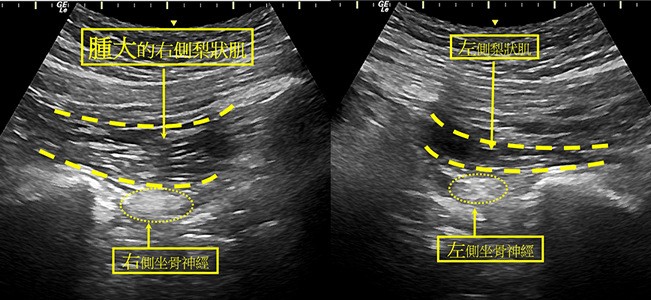

左圖:針對梨狀肌症候群病症,王柏凱醫師為病人進行「神經阻滯治療」,注射麻醉藥配合微量類固醇至患部,疼痛症狀立刻得到緩解。

右圖:透過超音波檢查,確診病人吳女士患有梨狀肌症候群,發炎的梨狀肌已腫大為正常的一倍。

吳女士透過復健與藥物治療數月,症狀都未改善,經人介紹,到花蓮慈濟醫院「疼痛門診」就醫。疼痛科主任王柏凱醫師透過高階精密超音波檢查、病史詢問、理學檢查,確診吳女士患有「梨狀肌症候群」,梨狀肌已經發炎腫大一倍。